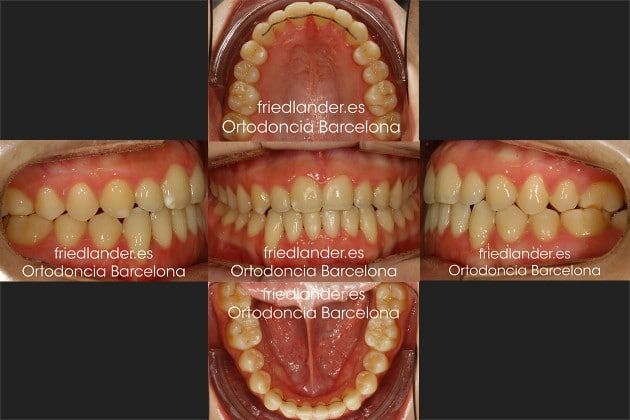

Explorando la boca de la paciente se puede ver que presenta una clase III de borde a borde (el maxilar superior es más pequeño). Todavía conserva los caninos de leche superiores e inferiores (también los segundos molares de leche) y se puede ver que el canino permanente inferior derecho se asoma por la encía entre los dos incisivos inferiores.

Esta paciente fue tratada con brackets convencionales y un disyuntor (aparato de expansión del paladar) durante 34 meses.

Hemos tenido muchas dificultades durante el tratamiento, sin embargo finalmente pudimos colocar los caninos en su sitio en la arcada con un estado de saludo de las encías bastante correcto.